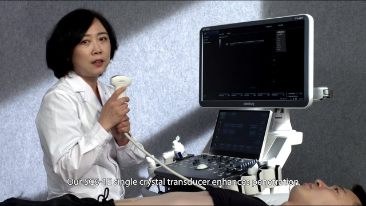

Le soluzioni Mindray Resona per la diagnostica per immagini generale consentono ai medici di ottenere diagnosi e trattamenti con risultati pi├╣ precisi ed efficaci grazie a sonde specifiche complete e a efficienti strumenti clinici applicativi.